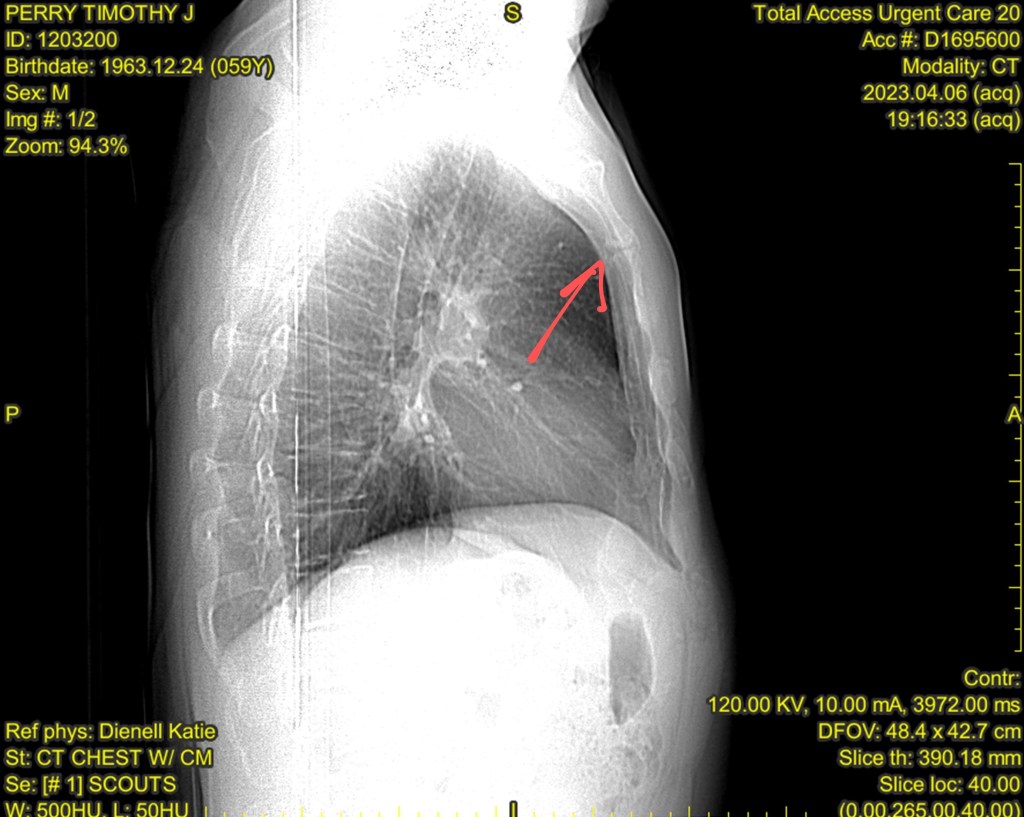

I would love it if you’d pray for that little cracked spot you can see in my chest in the image above – my cat Aspen knows right where it’s at! I broke my sternum! Broken sternums really hurt! I’m so grateful for Cheryl’s family who came to my aid in St. Louis. The accident happened at about 5;15pm. My nephew Will was able to come help me empty out my Accord and take me to the urgent care. Urgent care sent me on to a trauma center at St. Louis U Hospital. Thankful for lots of attentive doctors and medical staff who checked me over.